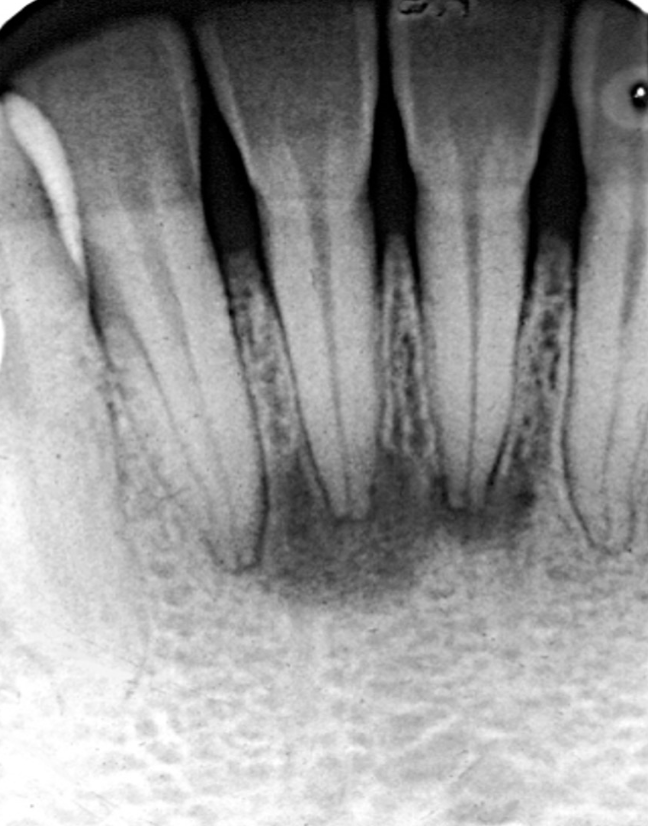

widening of PDL space

loss of lamina dura definition

different radiographic presentations of apical periodontitis

external resorption → irregular root surface

hypercementosis → bulbous-shaped roots